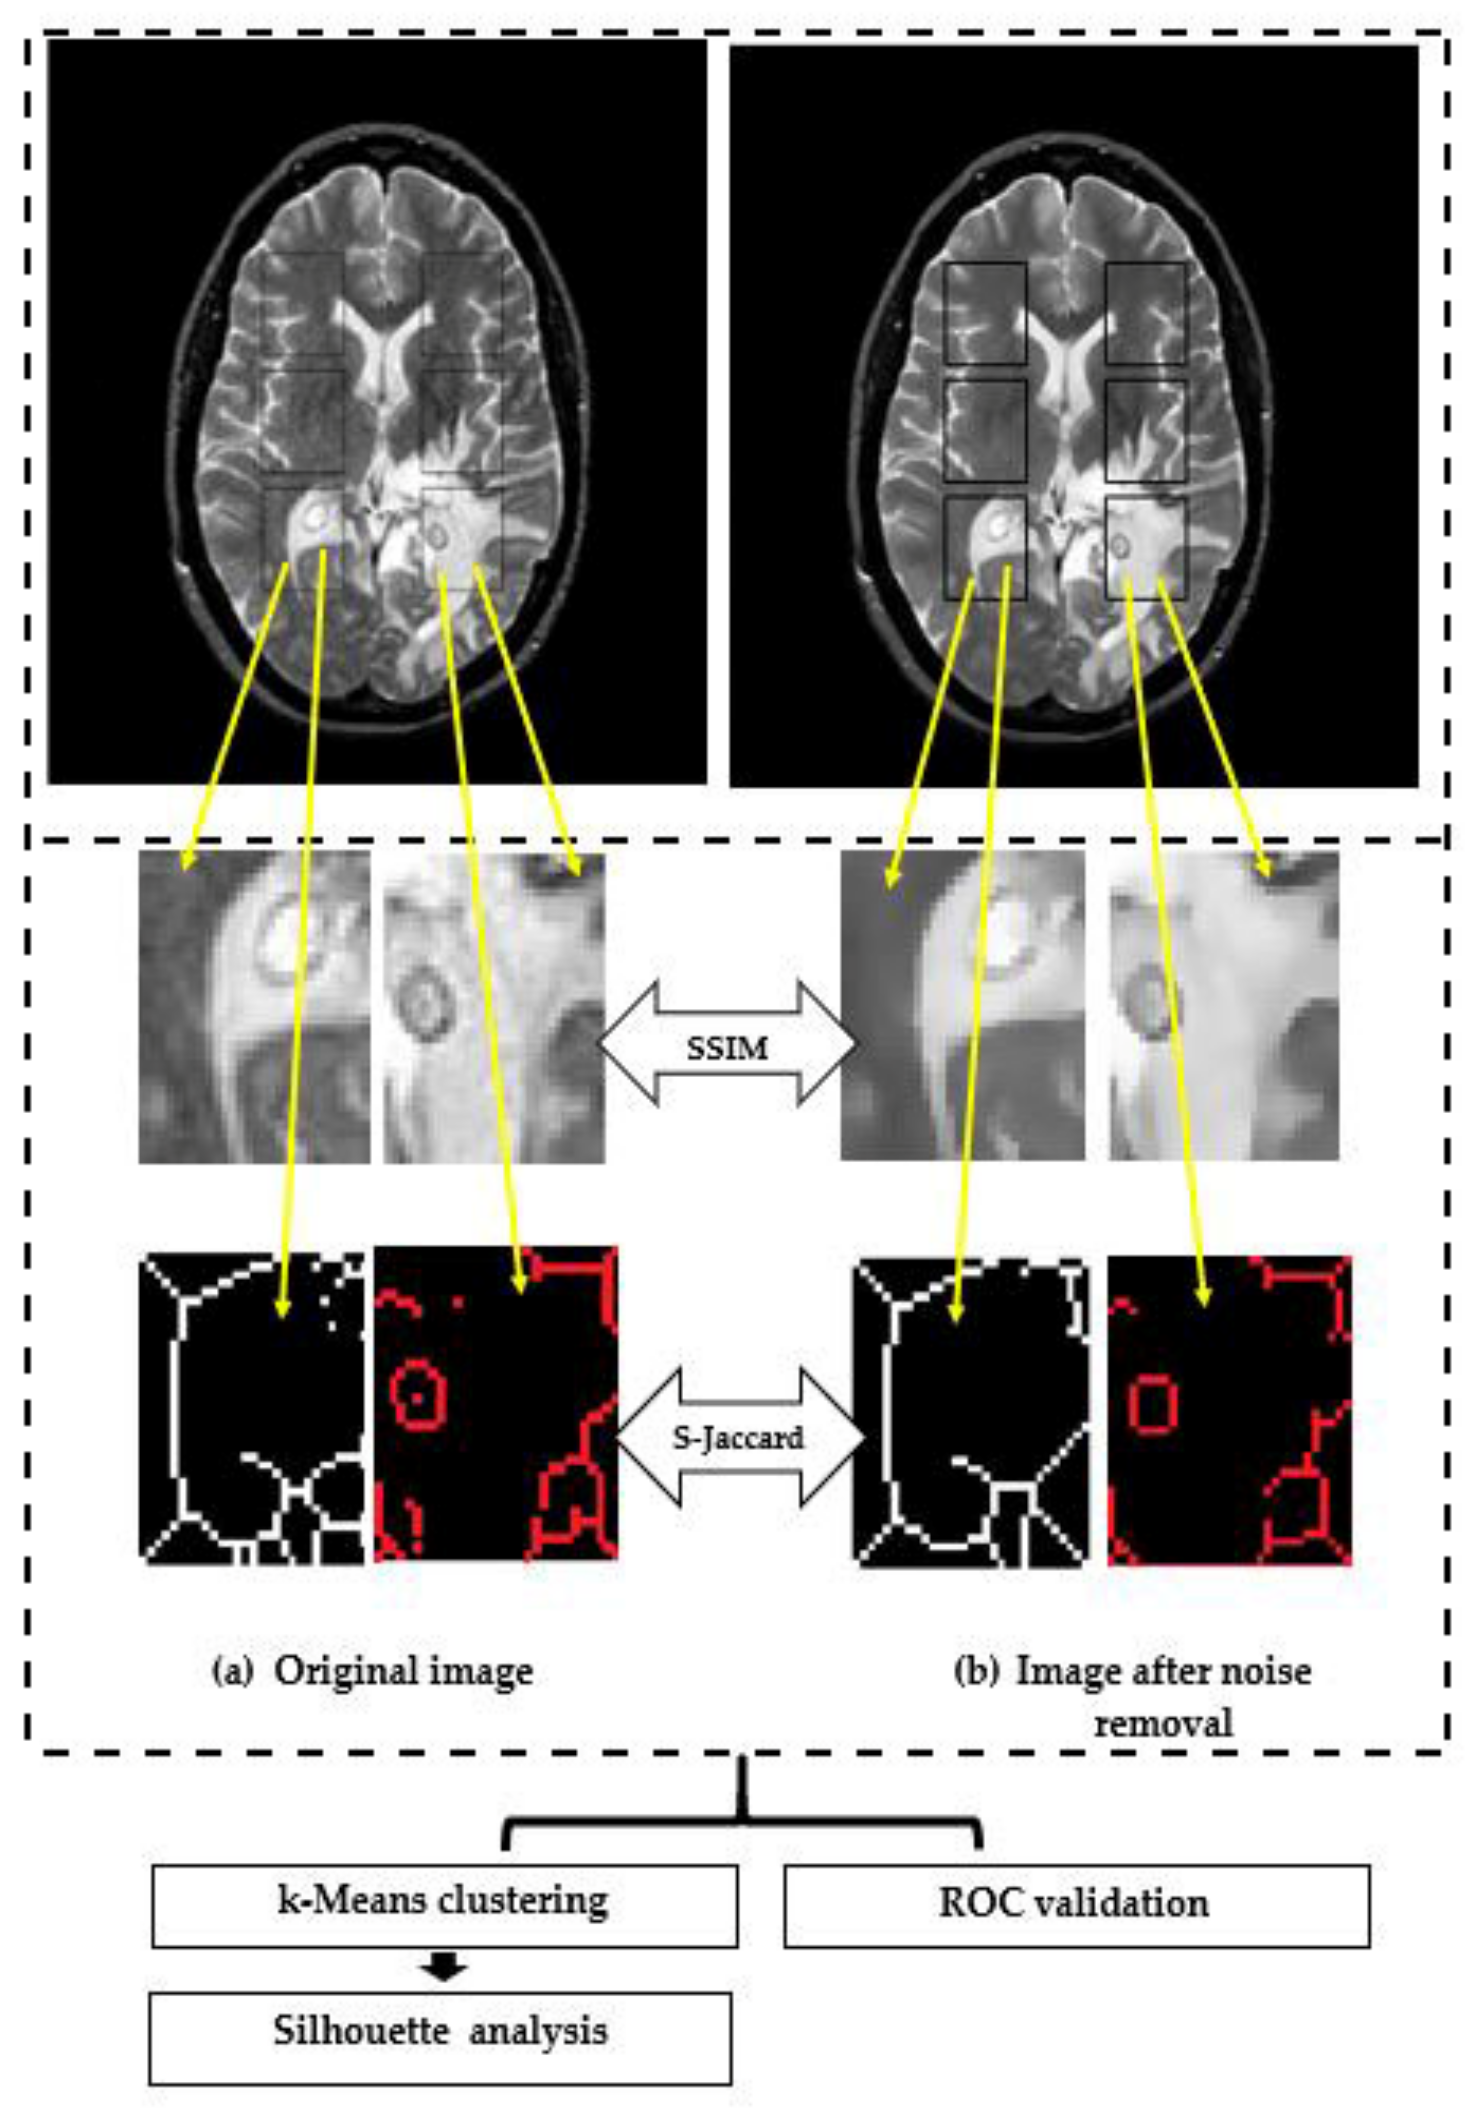

Figure 2 and Figure 3 show examples for the implementation of SSIMs and skeletonization for right– left correspondents for a raw image containing Rician noise (left panel) and a filtered image by the anisotropic diffusion filter (right panel).

Figure 2. Example of extracting regions of interes ROIs in proton density PD image for a patient with glioma, where: Left side: (a) raw image. Right side: (a) denoised image. (b) ROI 1L; (c) ROI 2L; (d) ROI 3L; (e) ROI 1R; (f) ROI 2R; and (g) ROI 3R.